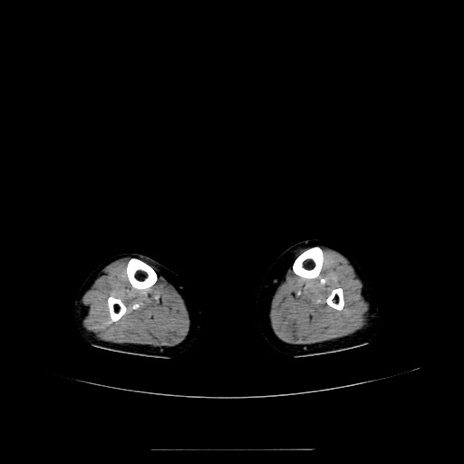

症例5(横断像)

【症例】70歳代女性

【主訴】お腹が張る

【現病歴】1週間くらい前から腹部膨満の自覚あり。昨日夜から増悪したため、本日救急外来受診。

【身体所見】意識清明、BT 36.5℃、BP 165/106mmHg、HR 80bpm、SpO2 98%、腹部:膨満、軟、自発痛・圧痛なし、触診にて不快感あり、腸蠕動音:減弱

【データ】WBC 12600、CRP 1.04